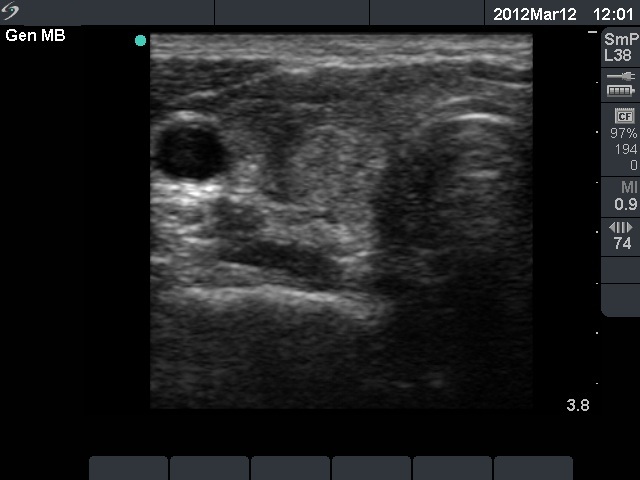

11 months after init. investig. |

7.30 |

0.18 |

4 months after delivery |

Nothing |

71 |

0.24 |

11.9 |

The relapse of de Quervain's thyroiditis in the contralateral lobe is a very frequent finding but not one year after the appearance of the disease. We supposed that the immunological changes during and after pregnancy explained the relatively late relapse of the disease.